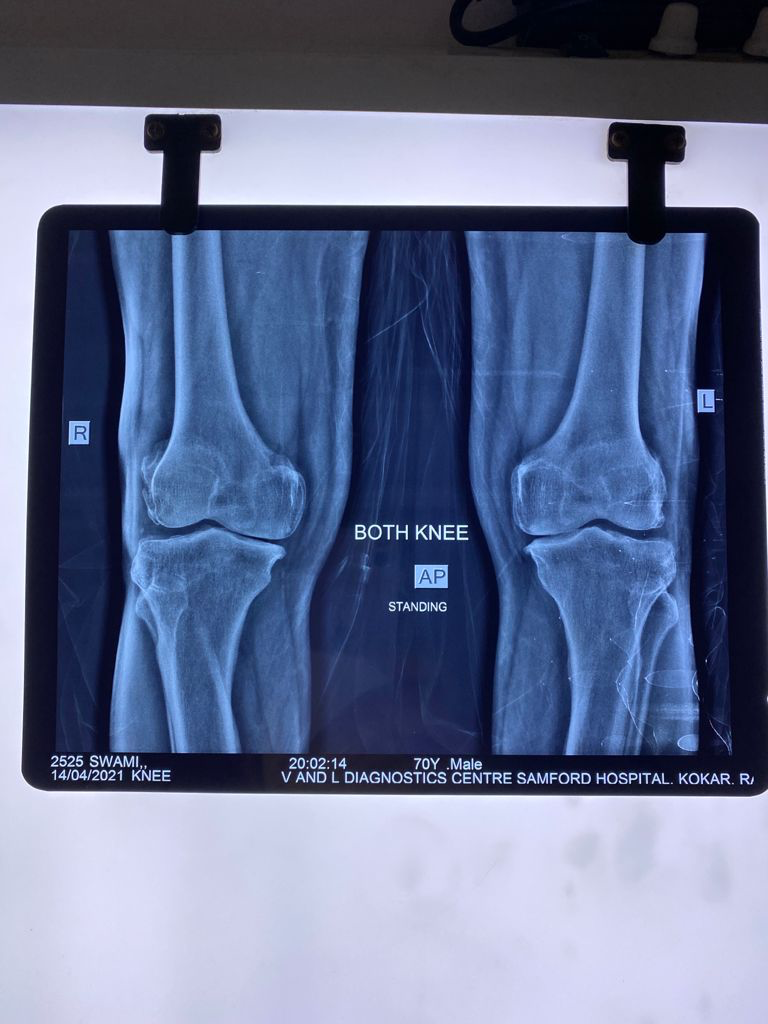

I am happy to say that after using Arthryt Pack for the past 7 years, the diagnosis changed! In 2021, the orthopaedic surgeon said that knee replacement is not needed for the rest of my life. Thanks to Arthryt Pack.

Recent X-ray (dated 14/4/2021) shows no further progression of OA.

April 2021

April 2021